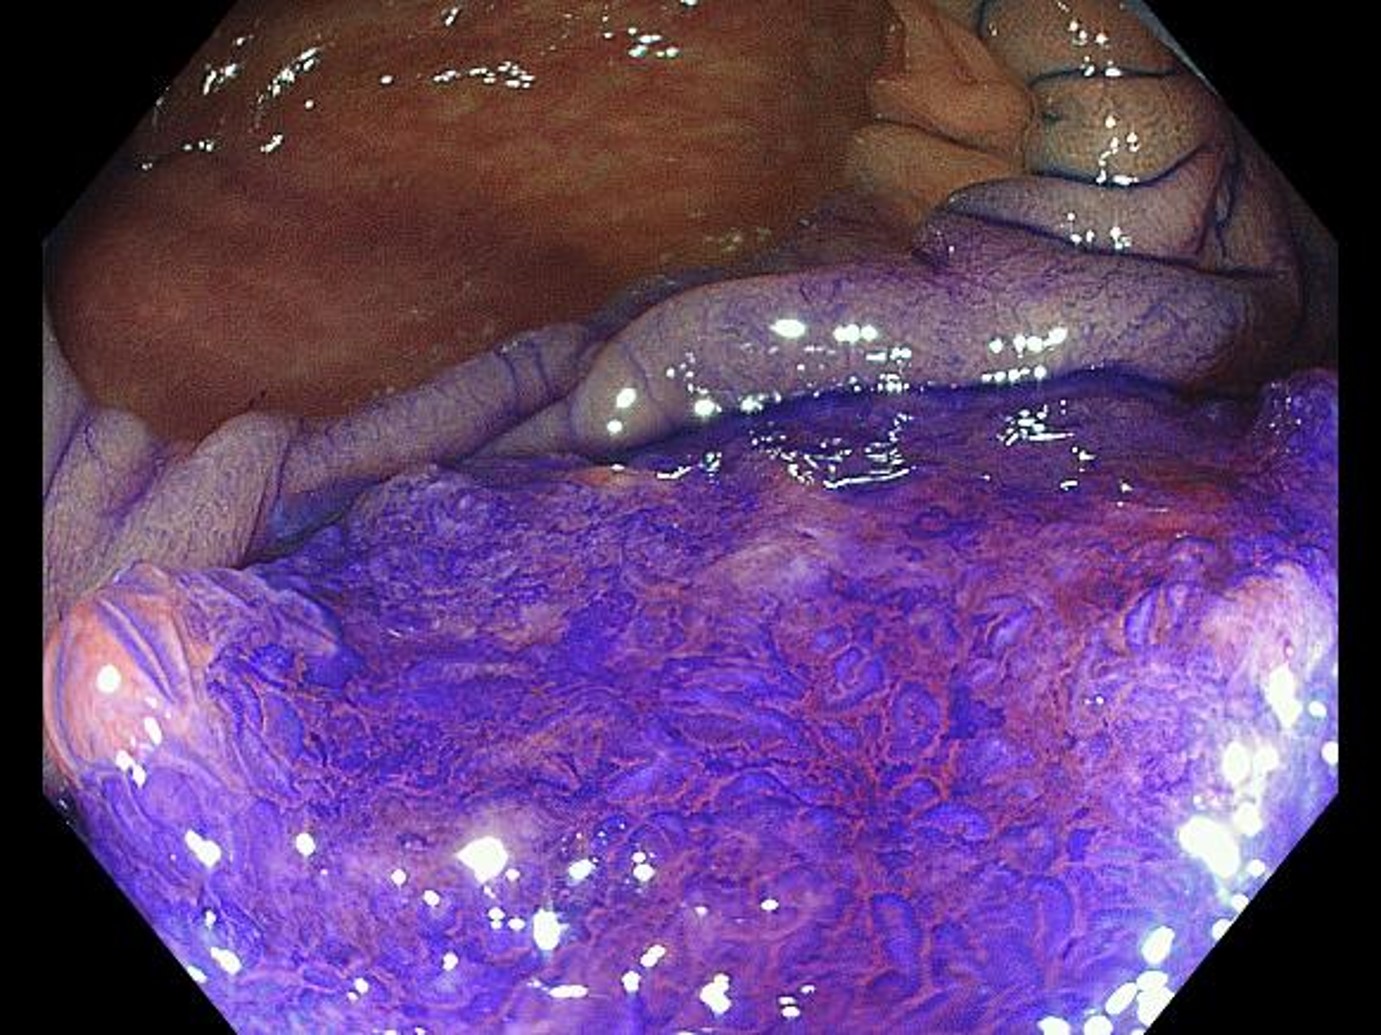

Magnifying chromoendoscopy (with crystal violet staining, in Near Focus mode)

While a highly irregular surface structure is recognized on the right of the image, a surface structure so damaged that it can be called structureless is recognized on the left. Diagnosis of pits is possible even in the Near Focus mode.